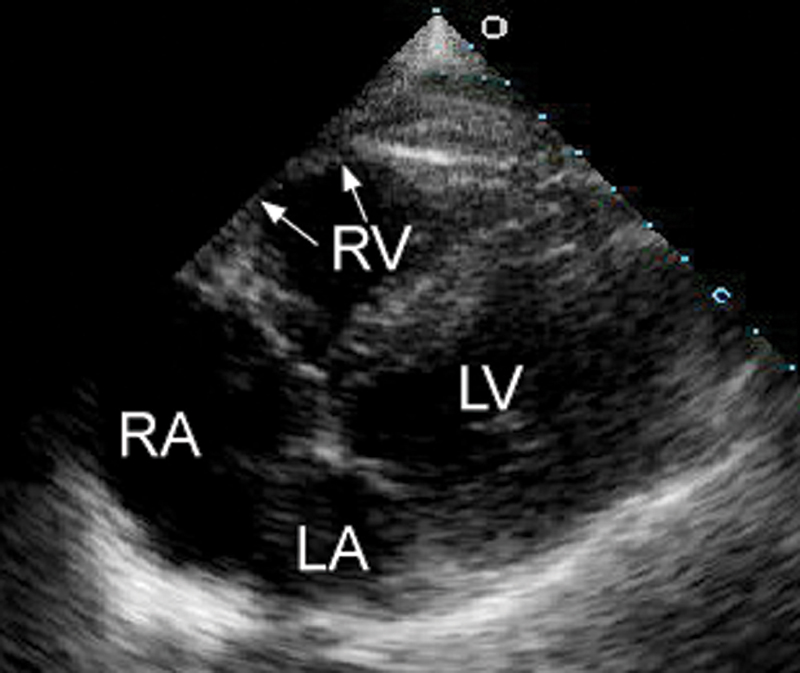

فحوصات تشخيصية لبعض امراض القلب والشرايين التاجية